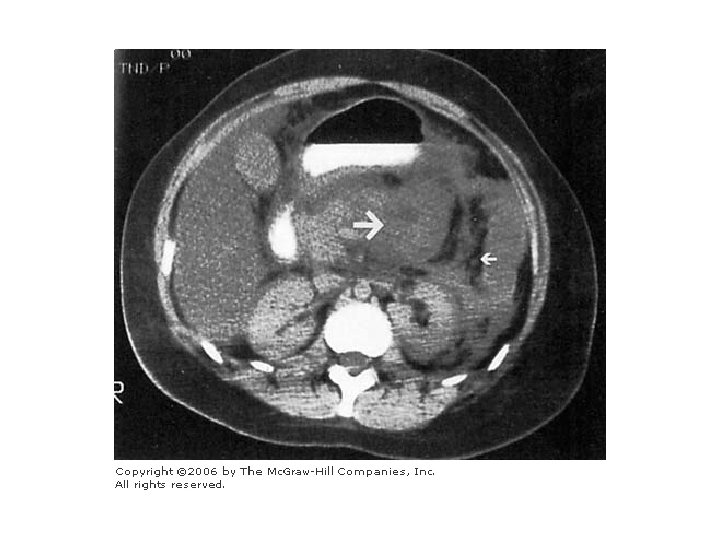

BT incelemesi • 48 -72 hr içinde pankreatitin gidişini değerlendirebilir • Flegmon, nekroz, psödokist, abse • Klinik gidiş ile ilişkili Balthazar sınıflaması

BT’de pankreas

Balthazar kriterleri. . . CT Skor endeksi = BT derecesi + Nekroz derecesi BT DERECESİ A: Normal pankreas B: Fokal yada diffüz pankreatik genişleme C: Pankreatik ve peripankreatik hafif inflamasyon D: Tek bir alanda( ön pararenal boşluk) sıvı birikimi E: İki veya daha fazla alanda sıvı yada gaz birikimi NEKROZ DERECESİ Nekroz yok Pankreasın 1/3’ünde nekroz Pankreasın 1/2’sinde nekroz Pankreasın ½’sinden fazlasında nekroz PUAN 0 1 2 3 4 0 2 4 6

İNDEKS MORBİDİTE MORTALİTE 0 – 3 4 – 6 7 - 10 % 8 % 35 % 92 % 3 % 6 % 17